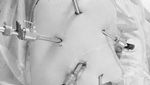

Dengan mempertimbangkan fungsi ginjal yang masih ada serta risiko gangguan aliran urin akibat ukuran batu yang besar, tindakan operasi dinilai rasional. Karena fungsi ginjal masih dapat diselamatkan, nefrektomi (pengangkatan ginjal) tidak dipertimbangkan. (Foto: BMC Urology)

Pemulihan pasca operasi berlangsung tanpa komplikasi. CT scan tindak lanjut yang dilakukan setelah 9 bulan menunjukkan keberhasilan tindakan. (Foto: BMC Urology)